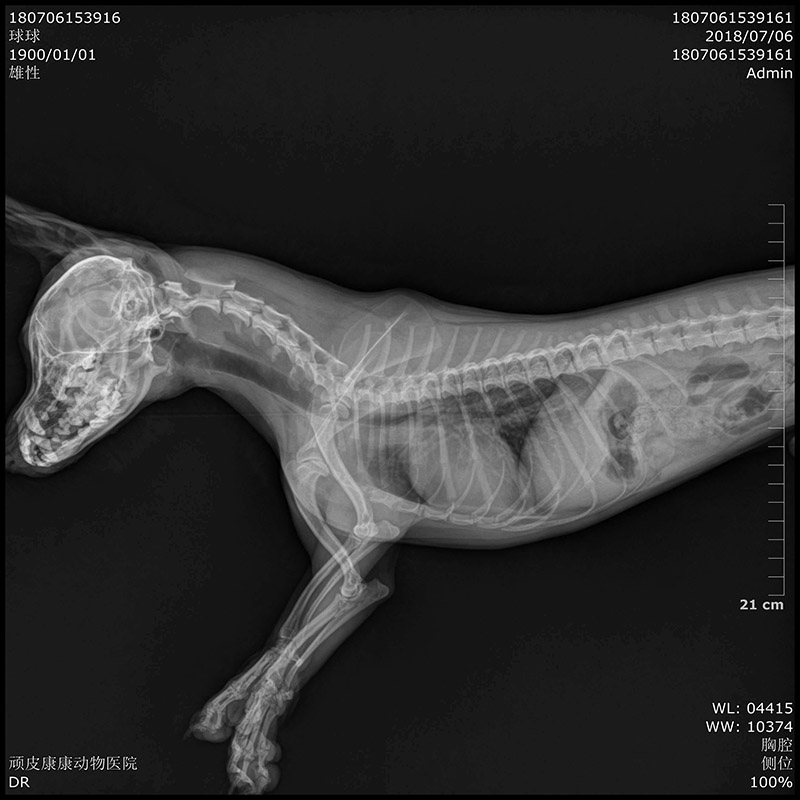

• Specification

• Clinical Image